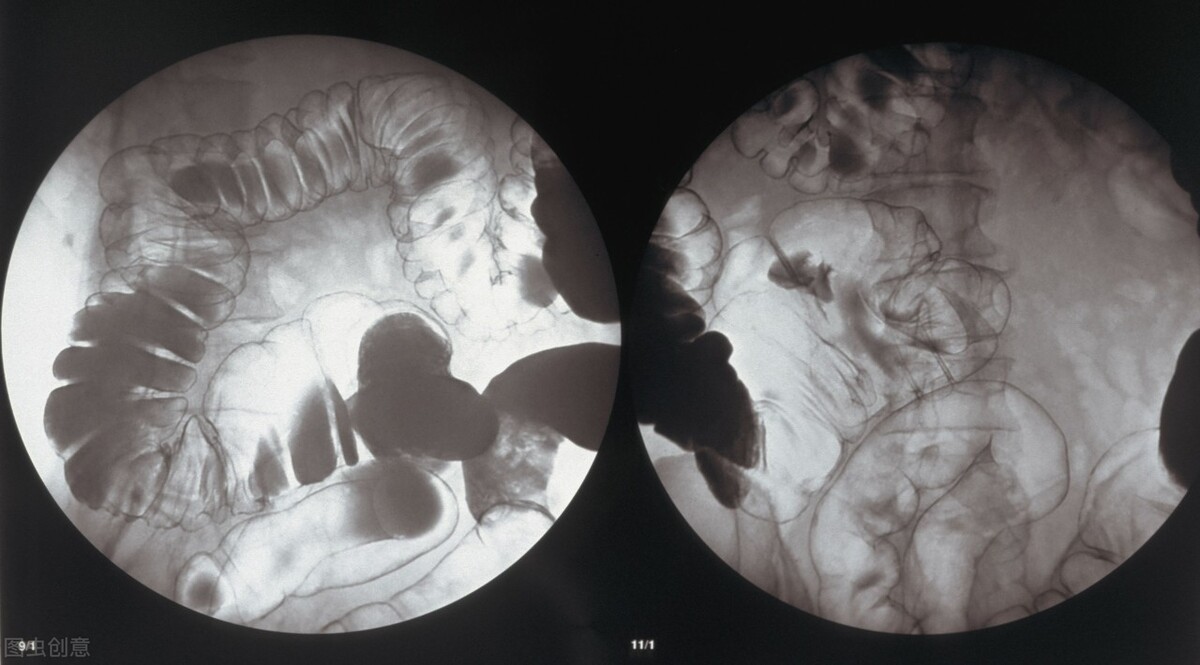

由于结直肠癌早期无症状,大家除了注意饮食等习惯及家族病史外,提早预防结直肠癌还有一项很重要的措施值得大家去做,就是定期筛检。目前香港无症状的61-75岁居民,可获免费资助筛检。结直肠癌好发于发达国家,因此美国癌症学会建议50岁以上的普通风险人群需做定期筛查,内容包括每五年一次乙状结肠镜检查,或每十年一次直肠镜检查,或每五年一次双钡灌肠造影以及每五年一次CT结肠镜检查。癌症并不可怕,大家保持良好生活习惯,定期筛检,早发现早治疗,终能战胜这些健康道路上的绊脚石吗。